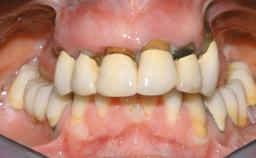

Immediate Loading of Eight Implants in the Maxilla and Six Implants in the Mandible and Final Restoration with Three-Unit and Four-Unit FDPs

Extensive scientific evidence has confirmed that immediately loaded implants with fixed full-arch provisional restorations can osseointegrate with success rates similar to conventionally or delayed loaded implants. A number of immediate-provisionalization techniques for edentulous jaws have been described. Some protocols differ when it comes to prefabricated provisional templates versus complete denture conversion; intrasurgical impressions versus direct relining; and cemented versus screw-retained provisional restorations. In this context, complete-denture conversion has been proposed for either intrasurgical impressions or direct relining. Another possibility is the utilization of a prefabricated provisional to be adapted either in the mouth (by direct relining) or in the laboratory (on a working model obtained from an intrasurgical impression).

Case Type Edentulous Maxilla

Jaw Maxilla and Mandible

Area Full-Arch